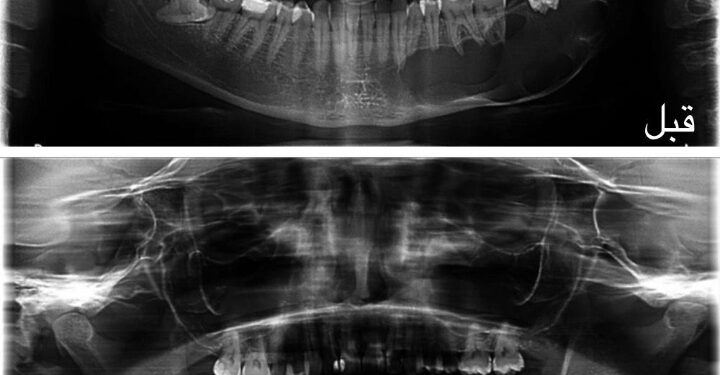

حقّق قسم جراحة الفم والوجه والفكين بمدينة الملك سعود الطبية عضو تجمع الرياض الصحي الأول إنجازًا نوعيًا يتمثل في ابتكار تقنية علاجية مبتكرة للأورام الكيراتينية في الوجه والفكين، حملت اسم تقنية السحيم والتريكي، نسبةً إلى مبتكريها د. فيصل بن سحيم ود. هيثم بن تريكي، استشاريي جراحة الفم والوجه والفكين.

وتتميّز التقنية الجديدة بنتائج غير مسبوقة، حيث نجحت في خفض معدل انتكاس الحالات إلى ما يقارب الصفر، مقارنةً بالطرق التقليدية التي كانت تصل نسبة عودة الورم فيها إلى أكثر من 60%. كما اختصرت الإجراءات العلاجية، إذ كانت بعض العمليات في الحالات المتقدمة من هذه الأورام تستغرق من 6 إلى 8 ساعات تحت التخدير الكامل، وتتطلب استئصال الجزء المصاب من الفك وإعادة بنائه بتكاليف مرتفعة، بينما قدّمت التقنية الجديدة حلولًا أكثر فاعلية وأقل كلفة.

يُذكر أن تطبيق هذه التقنية بدأ منذ عام 2013م، وتم خلالها علاج عدد من المرضى بنجاح كبير، مما يؤكد فعالية هذا الابتكار وجدواه في تعزيز جودة الرعاية الصحية، مع إمكانية توسيع تطبيقه مستقبلًا لعلاج أورام مشابهة في مجال جراحة الفم والوجه والفكين.